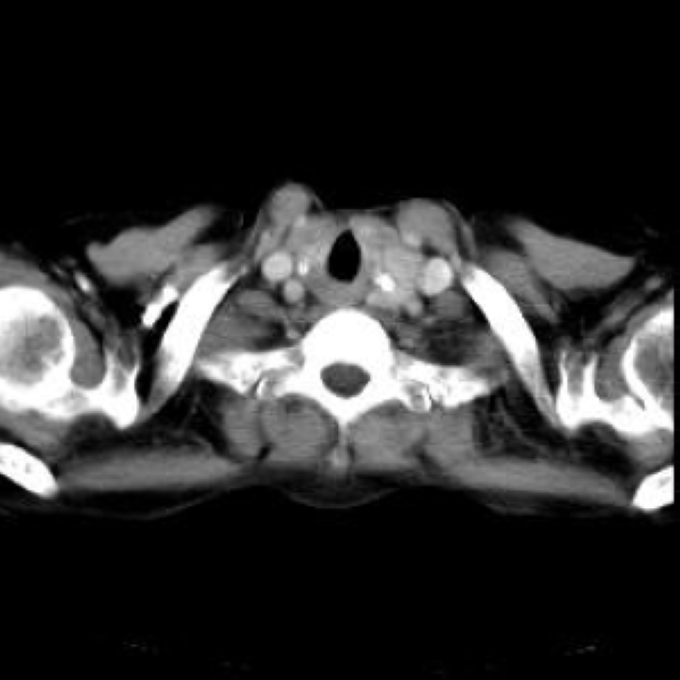

Arteria lusoria.

56 year old patient with dyspagia. A tumor of soft tissue was described in upper mediastinum on plain X-ray of the thorax. What is this mass in the upper mediastinum?